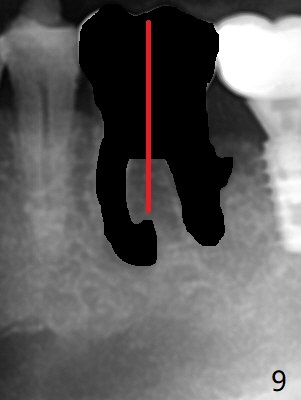

Venopuncture is conducted (Fig.1) for PRF and sticky bone (cortical chip and .5 cc ß-TCP). After use of proximators at #19, cowhorn forceps are applied, resulting in metal crown dislodgement. Since there is distal bone loss, distal socket sheath is contemplated. The tooth is sectioned. When an elevator is inserted between the roots, the distal root is loosened first. The 2 roots are removed, revealing a rounded end septum (Fig.2 S) and a larger distal socket. To avoid osteotomy deviation over the septum, a 12 mm bone trimmer is used, followed by point drill (Fig.3 *). But the lower half of the implant is deviated mesial (Fig.4) with decreased torque (~ 10 Ncm). To overcome this misfortune, the roots should not be removed until osteotomy is finished. Dual zones of bone graft is conducted. Sticky bone is placed until the plateau of the implant with a healing screw in place (Fig.4 * (bone zone)). After placement of a pair abutment, the same bone graft is packed until the margin of the abutment (Fig.5 * (soft tissue zone)). An immediate provisional is fabricated to close the socket with a piece of PRF as well. Fig.6-11 explains why the lower half of the implant deviates to the mesial socket, while Fig.12-16 illustrates how to prevent the deviation. After extraction of #19 (Fig.6,7), the crest of the septum is flattened (Fig.8 arrowhead) to prevent the initial deviation (Fig.9 red line). When a drill reaches a space (a socket, mesial in this case), the drill is deflected to the least resistant area (Fig.10 a bent red line), leading to the implant deviation apically (Fig.11 green). To prevent the apical deviation, therefore, the roots of the affected tooth is temporarily not removed (Fig.12). The osteotomy should not deviates with surgical guide because of similar density between the tooth and the bone (Fig.13). When the osteotomy is finished (Fig.14), the roots are extracted (Fig.15). The implant to be placed should not have deviation (Fig.16 green). The papillae are maintained by the immediate provisional 11 days postop (Fig.17). The incompletely seated abutment at #18 (Fig.5 <) is reseated completely 6 months postop (Fig.18). Crestal bone forms distal to #19 implant. There is no bone loss 4 months and 3 years 1 month post cementation at #19 and 18, respectively (Fig.19,20).